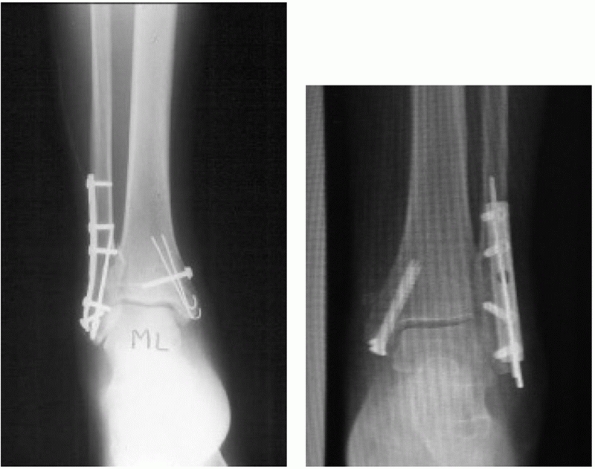

that each fracture be evaluated on a case-by-case basis. Significantly